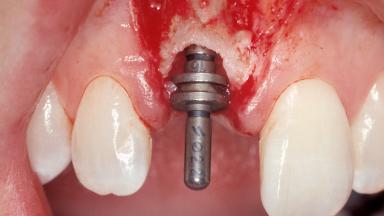

A 30-year-old female patient was referred to the office for the treatment of tooth 11. Her chief concern at the initial visit was to inquire, “Why is my tooth pink?” Upon clinical examination, it was determined that tooth 11 had a previous history of trauma and that the clinical crown had become noticeably pink in color as a result of internal resorption. This diagnosis was confirmed radiographically, indicating a large radiolucency involving the central and distal portions of the clinical crown. It was determined that restoration of this tooth was not possible, and that extraction was indicated. The presence of a mid-line diastema, which the patient wanted to reproduce, directed the treatment plan for tooth replacement utilizing a dental implant.

Placement Protocol Immediate implant placement

Tooth Site Maxillary incisor or canine

Socket Morphology Single-root socket

Socket Integrity Sufficient, with intact bone walls

Bone Volume Sufficient, with intact walls